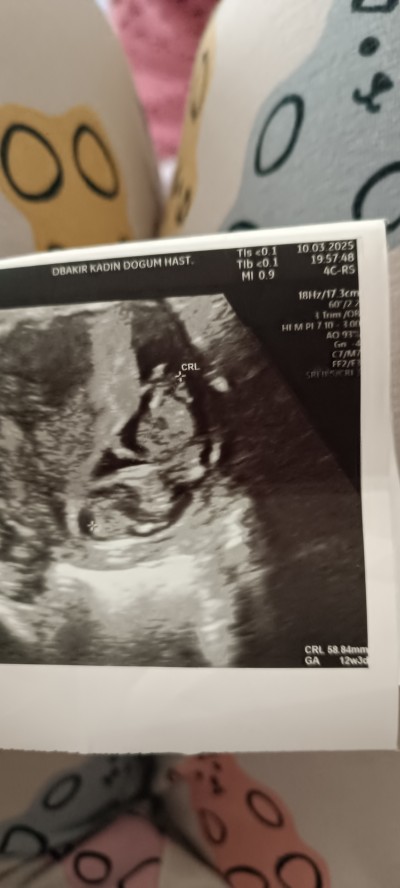

Buyur canım

image

Benim ki ne acaba